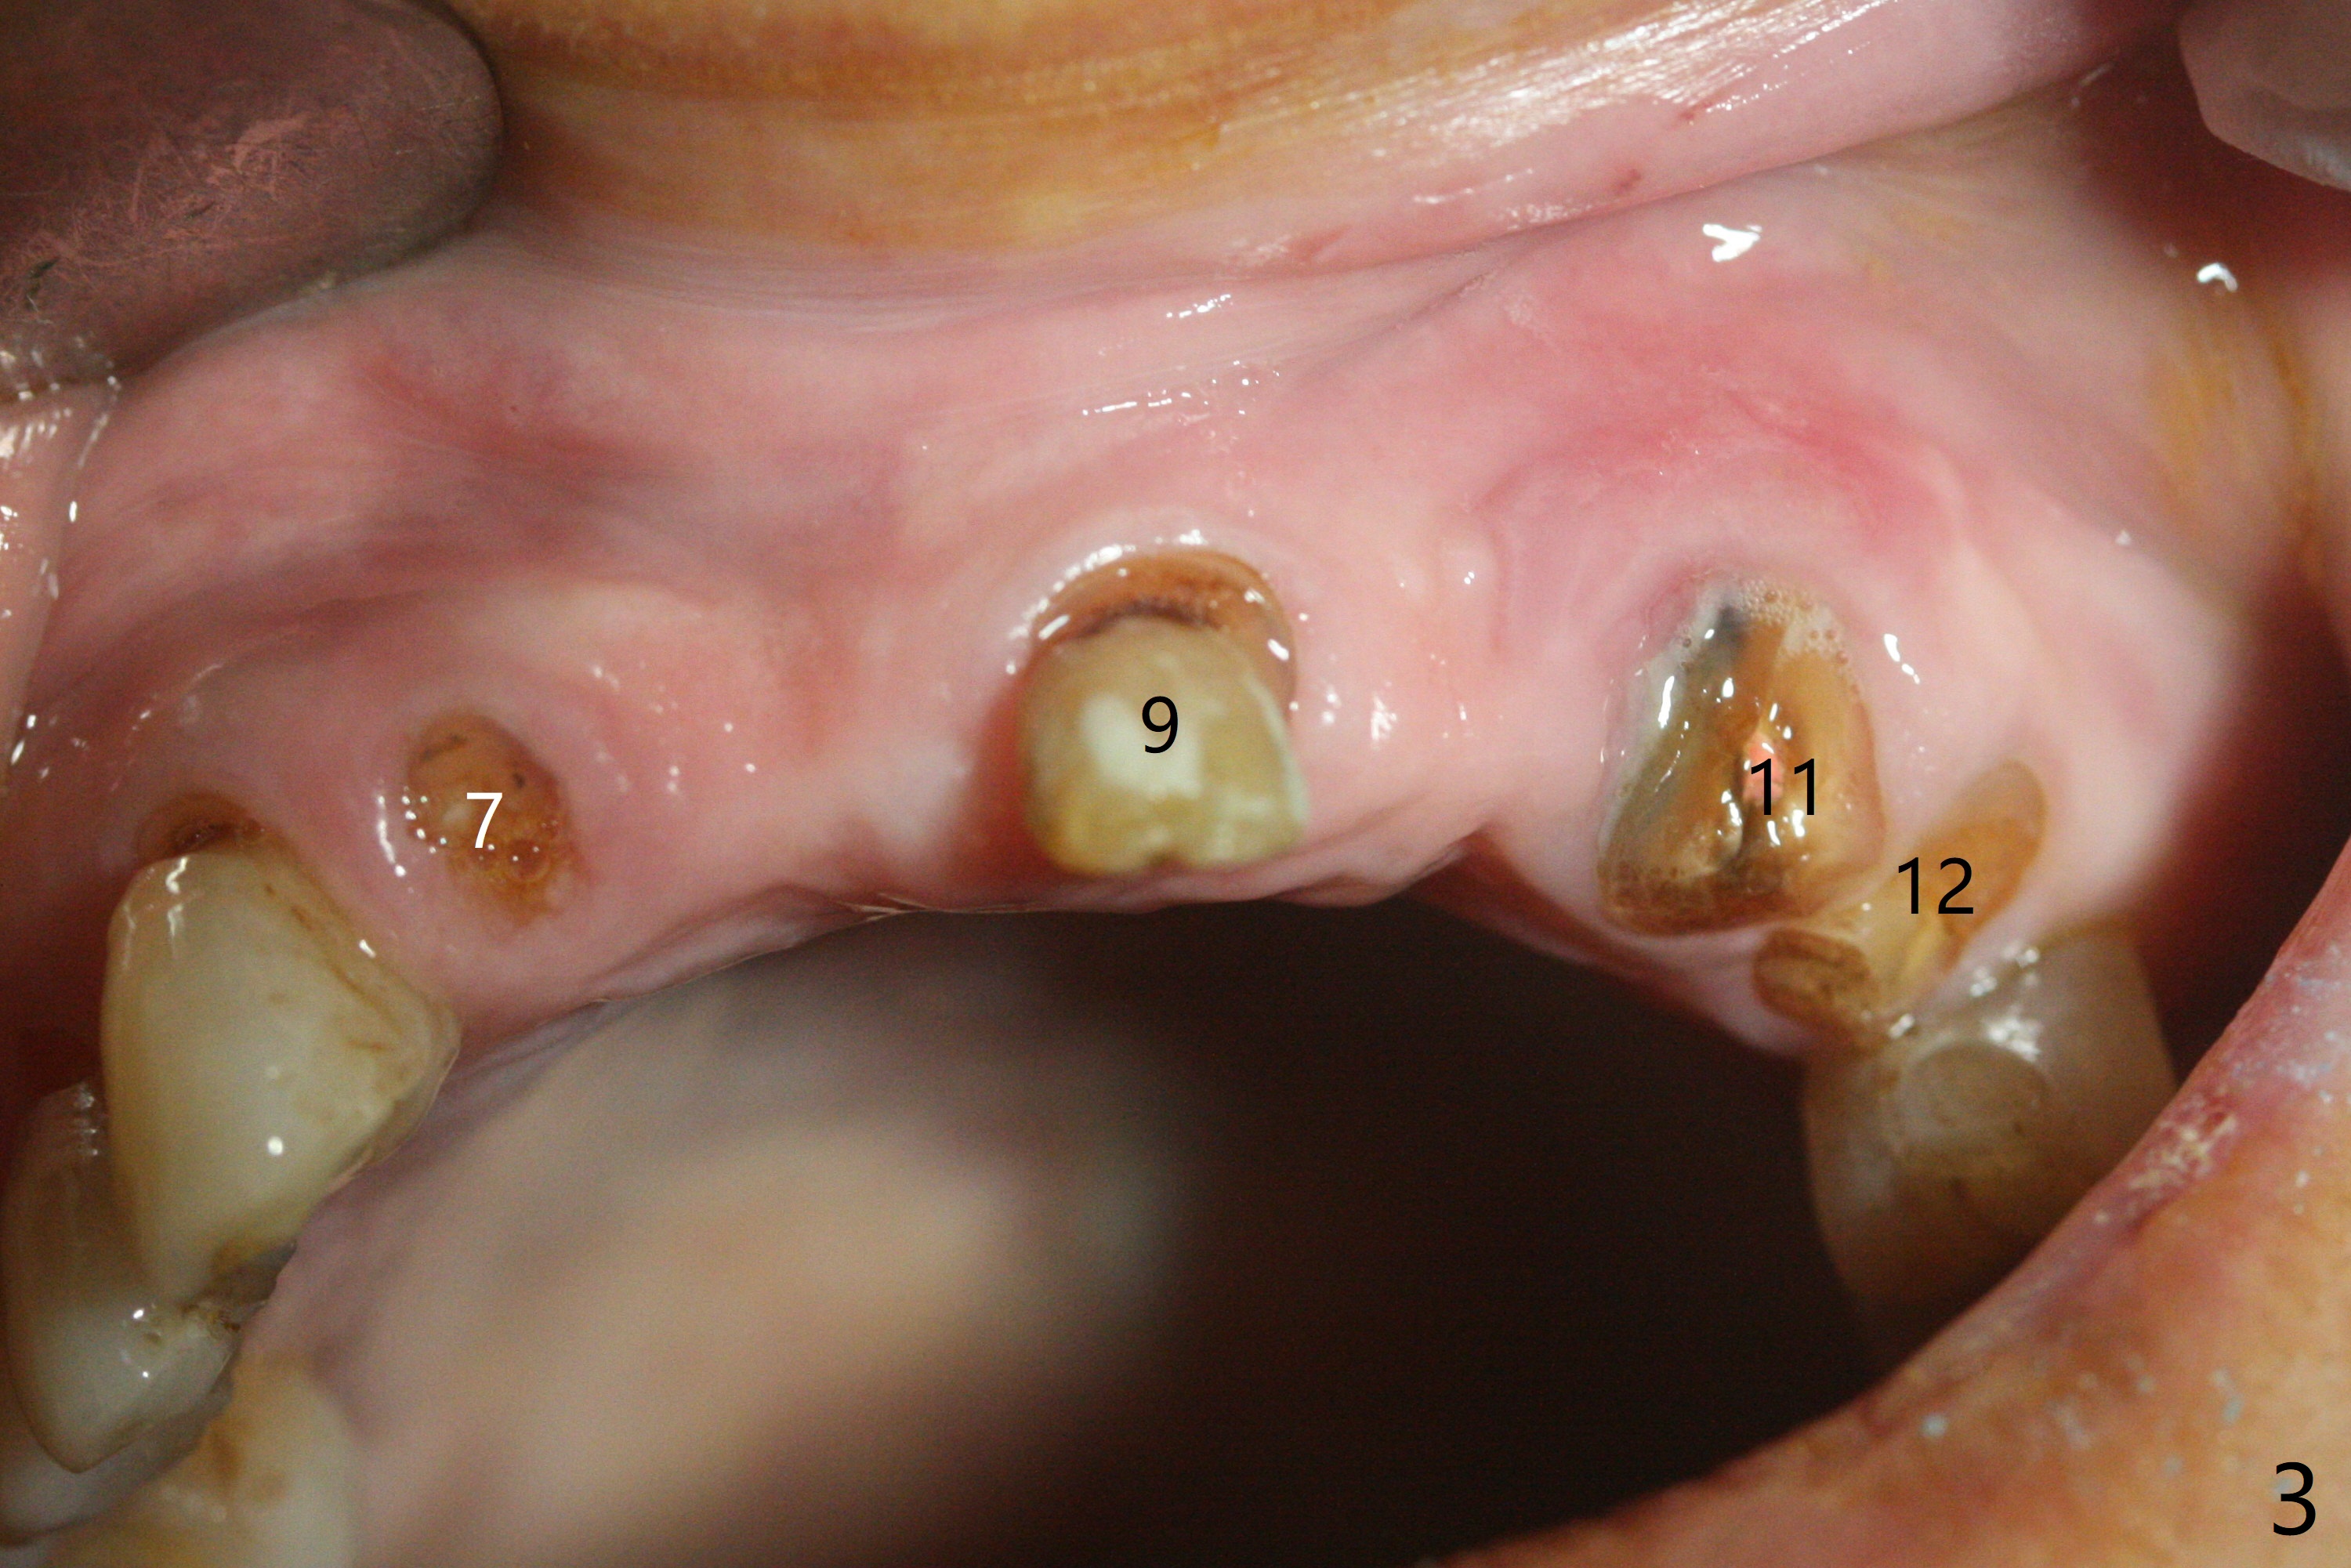

今天下午进入治疗室,粘性骨粉已制备:上清液来自红管(含促凝剂),离心3分钟(图一);再离心10分钟上清液就转变PRF,压制后,使用前剪成三块(图二:黑线),其中两块punch一个洞(图二:圆圈),插入7,9号牙基台固定;大块覆盖11/12号牙牙槽窝(图十四)。7,9,11,12号牙必须拔除(图三),然后在7,9,12种植。由于缺失左下磨牙,前牙垂直距离减少(图四)。完成9号牙位钻洞后,利用fixture mount(图五:M)植入植体,并留在原位固定导板(图六),然后7号牙种植,也留下fixture mount(图六:7,9),最后完成12号牙植入,但是后者扭力低,放置愈合螺帽(图九),而7,9号牙位放置修复基台(图七,八(使用5.5毫米profile drill后),好像基台没有完全就位。7号牙位更换基台似乎没帮助(图十),9号牙位再次放置同一个基台临床上仿佛有改变(比较图八与十二)。放置粘性骨粉后(图十一至十三),牙槽窝口覆盖PRF膜(图十四:P(A:基台)),最后使用树脂敷料固定骨粉和膜(图十五,六),基台帮助敷料固位,没有咬合干扰(图十七:*)。树脂敷料部分解决美观问题,一个月后撤除,如果植体仍有稳定性,可能制作7-10临时牙桥,可能部分维持或者恢复牙龈外形。术后一周病人主诉后面植牙和鼻底疼痛,11号牙根尖牙龈充血(图十八),轻度触痛,可能与术中尚未完全清创有关(图十九(术前CT 3D图像))。再服用Amoxicillin一周,症状好转,鼻底轻度触痛(图二十)。术后1.5月没有任何不适,撤除树脂敷料,7号牙基台(袖)显得太长,换一个短的(4.5x4(5)(图十,十一)->4x4(3)毫米)毫米),植骨好像愈合正常(图二十一:*)。7号牙换了短的基台,9号牙基台高度调整后,与对合牙有足够空间做临时牙桥,最好8,10号牙位牙龈应该凹陷(图二十二:*),有pontic外形。另外9号牙基台颊侧牙龈边缘有所修整,临时牙桥准备。先做7-10临时牙桥,理想临时牙桥pontic处树脂应该多些(图二十三:白线)压迫牙龈形成凹陷。11,12号牙牙槽窝在树脂(Bosworth)敷料下也正常愈合(图二十四)。